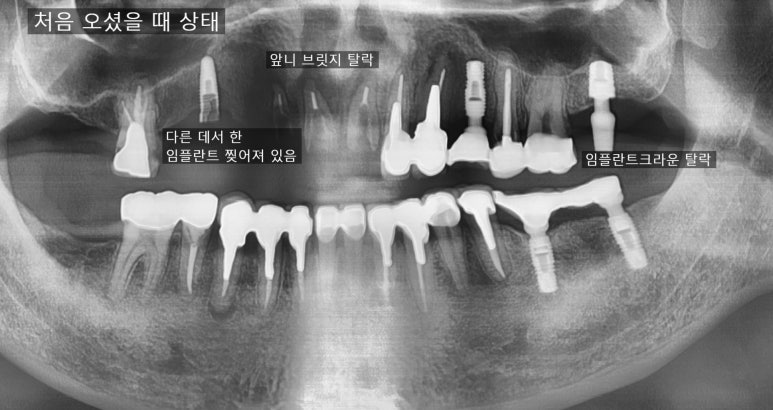

처음 오셨을 때 상태

앞니 뿌리쪽까지 많이 썩어서 삭아 들어가서

앞니 브릿지가 붙을 곳이 없어서 흔들거리고 빠져서 온 상태입니다.

어금니쪽도 다른데서 한 임플란트가 찢어져서 임플란트 머리를 못 올린 상태였고

어금니도 몇 개 상실한 상태입니다.

치료전( 앞니 브릿지 떨어져서 덜렁이는 상태, 다른 곳에서 임플란트 찢어져 실패해서 잇몸에 묻혀진 상태)